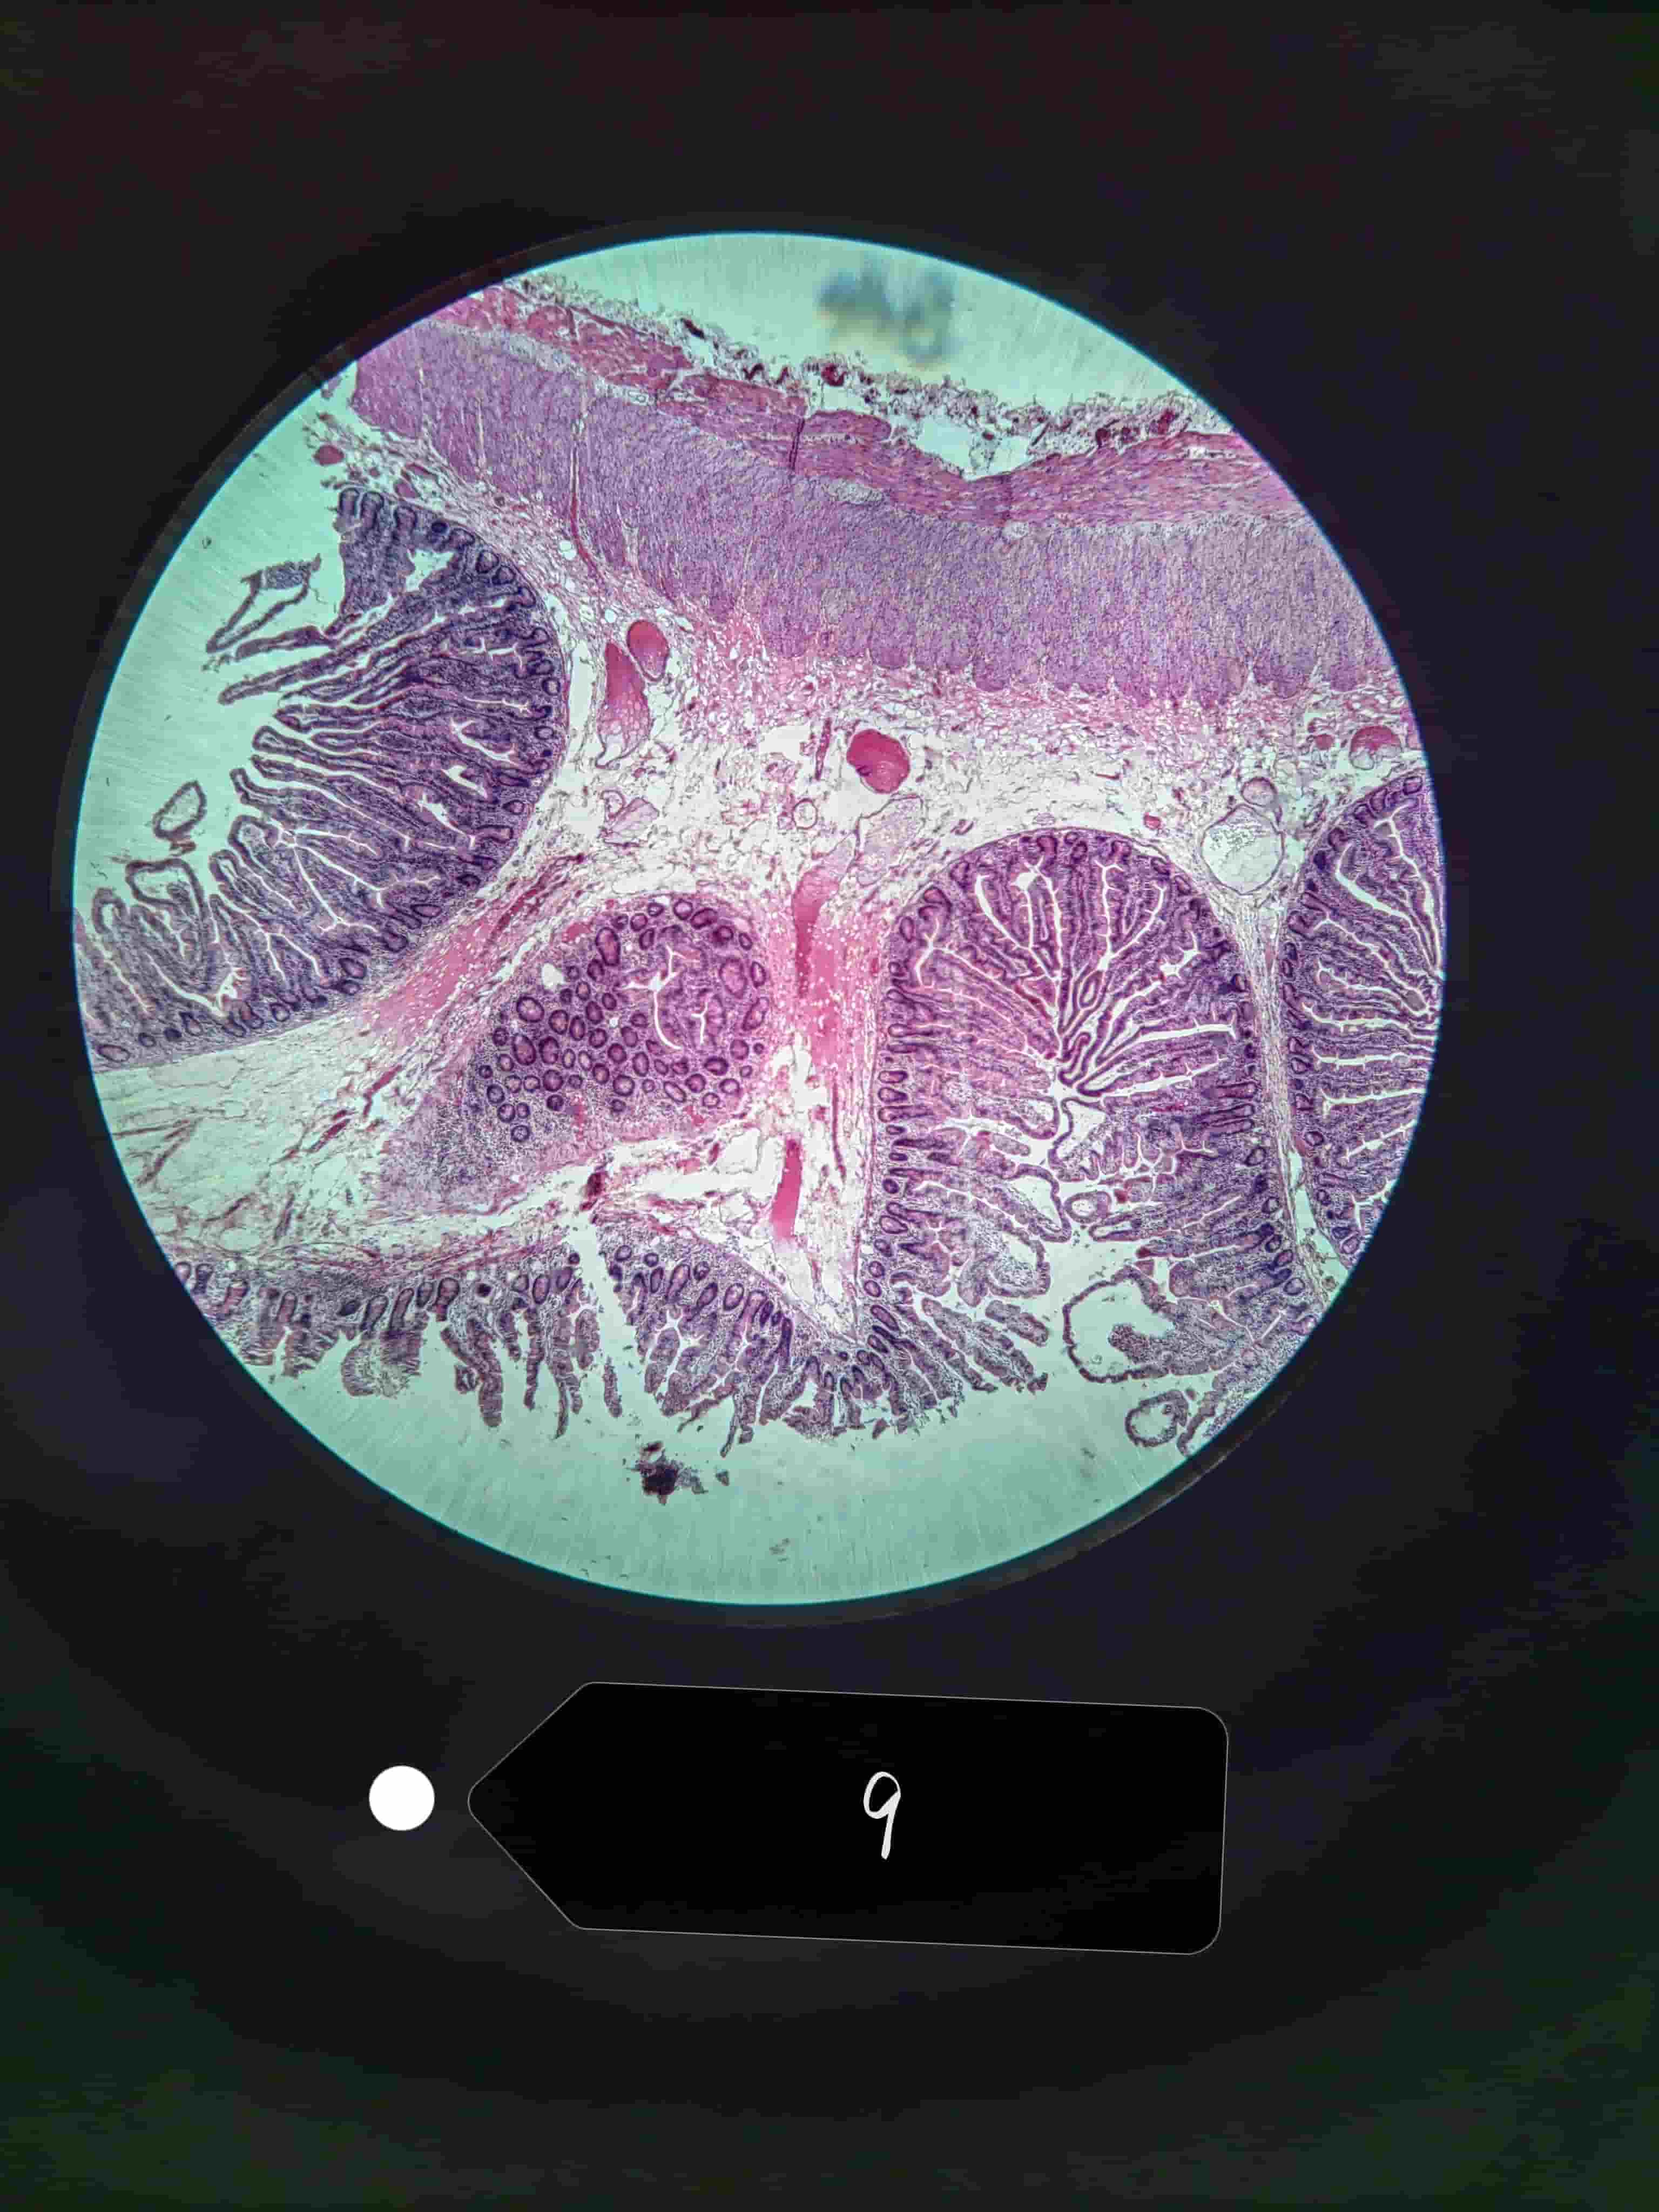

小肠

小肠绒毛

小肠腺,潘氏细胞

大肠

大肠腺

单层柱状上皮,杯状细胞较多